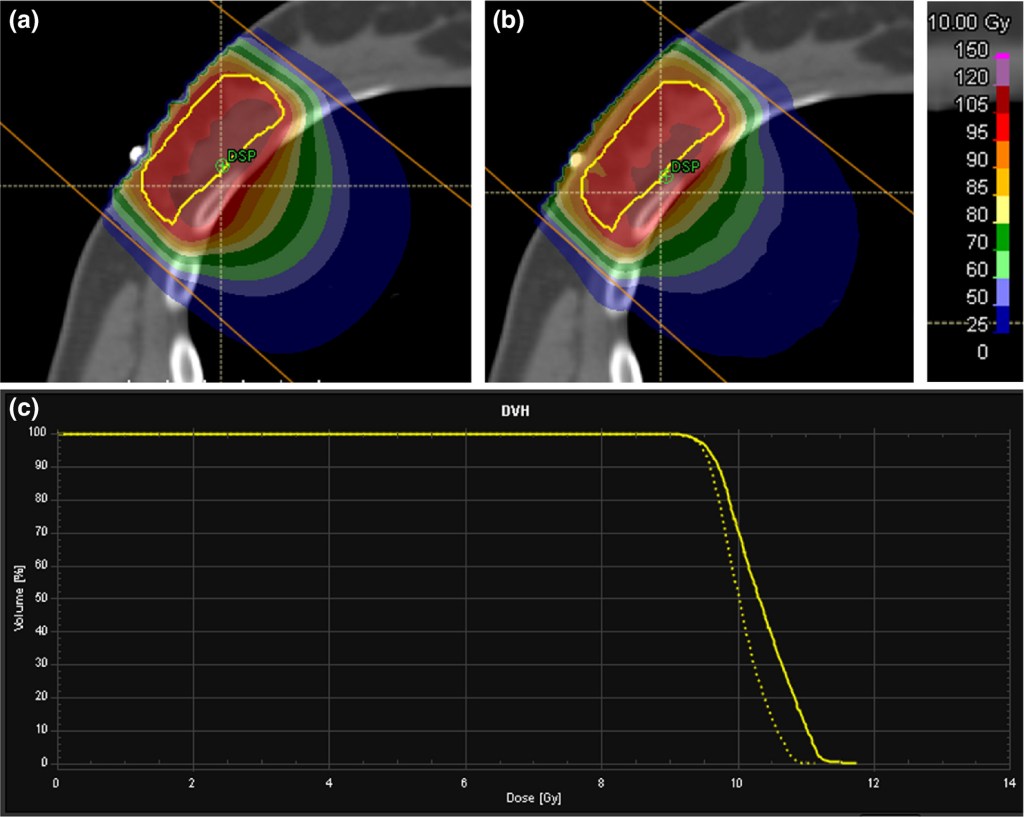

Traditionally, radiation dose distributions have been calculated using Monte Carlo simulations. While highly accurate, this method can be computationally intensive, posing challenges for real-time clinical applications. Ultra-Fast Monte Carlo technique harnesses advanced algorithms and powerful GPU acceleration to expedite the process without compromising on precision.

The introduction of Ultra-Fast Monte Carlo Dose Calculation brings numerous advantages to radiation therapy planning. By leveraging the capabilities of GPU acceleration and optimizing algorithms, the process significantly shortens the time needed for dose calculations. This translates to reduced waiting times for treatment plans, allowing clinicians to evaluate plans more efficiently. Moreover, this technique maintains the highest level of accuracy, ensuring patients receive safe and precise radiation therapy.

To further optimize the process, hybrid approaches have been integrated into the Ultra-Fast Monte Carlo Dose Calculation. By combining the strengths of Monte Carlo simulations with deterministic methods, such as pencil beam algorithms, to strike a perfect balance between speed and accuracy. This integration guarantees that patients receive tailored and effective treatment plans, all while maximizing resource utilization in clinical settings.